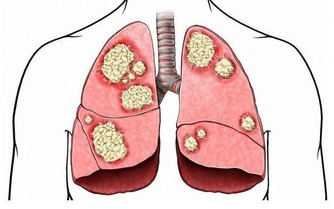

photos 其他預防方法:改善自我體質! 1. 益生菌:以Lactobacillus為主 (rhamnosus, casei and other species),確實數據上有: 降低感染的次數 已經感染時不舒服的天數 降低抗生素的使用 降低小朋友學校的缺席率(這竟然也有統計!?) 2. 口服或鼻用鋅的補充:10/15mg每天(不過每個研究吃的量差異很大),有機會減少感染天數和嚴重度。 3. 漱口:建議用水(日本是用生水因為含氯,但在台灣我還是建議開水好些)或含碘的漱口水漱口(市面上有專用配方)。一天4次,一次30秒以上,可以帶走/殺死致病的細菌或病毒,其實也算是切斷感染途徑。個人比較不喜歡酒精性的,殺菌性較不確定,且口感偏刺激些。理論上含氯的漱口水也可以,但相關研究較少。

以下是單就「預防感冒」而言是比較還好的: 1. 多運動:對感冒的發生率、嚴重度、發病天數相較之下較沒有明顯差異(不過多運動對長期心肺功能的改善和整體身體狀況還是很重要的,絕對不是叫大家不要運動。) 2. 維他命C:200-3000mg/天。對大部分人較沒明顯效果,官方多建議直接從五蔬果補充(但一樣,這是單就「預防感冒」,對身體健康而言還是要吃。) 3. 洗鼻子:對改善感冒症狀有效,預防角色還未知,需再研究。 4. 大蒜萃取物、人參等:預防角色還未知,需再研究。 以上方法若執行確實,能將被感染可能性降到最低,但不是杜絕。若真的身體有不適,還是要就近看醫生。